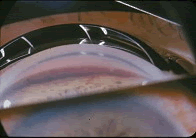

患者,女性,24岁,右眼胀痛2天。检查,右眼视力0.9,角膜透明,前房深,房水闪辉阴性,瞳孔对光反应好,房角见睫状体带较右眼宽(如图),右眼眼压30mmHg。1个月前有右眼钝挫伤史。最可能的诊断是()

- 虹膜炎继发性青光眼是由于( )。